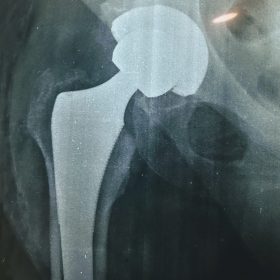

Παραδοσιακά οι αρθροπλαστικές ισχίου αποτελούνται από μια μεταλλική μπάλα – σφαίρα τοποθετημένη σε μια πλαστική κοιλότητα (κοτυλιαία πρόθεση).

Η πλαστική επιφάνεια στήριξης φθείρεται με την πάροδο του χρόνο, με ρυθμό μάλλον σχετιζόμενο με το επίπεδο δραστηριότητας του ατόμου. Αυτό έχει σαν επακόλουθο νεότεροι ασθενείς με μεγαλύτερο προσδόκιμο ζωής να έχουν αυξημένο ρίσκο αναγκαιότητας δεύτερης αρθροπλαστικής ισχίου (αναθεώρησης – Revision) επέμβαση που είναι πολυπλοκότερη και υπόκεινται σε υψηλότερο κίνδυνο επιπλοκών. Βάση των ανωτέρω, ιστορικά, η αρθροπλαστική ισχίου σπανίως εφαρμοζόταν σε ασθενείς κάτω των 60 ετών.

Χάρη στα νέα τεχνολογικά επιτεύγματα έχουν παραχθεί επιφάνειες στήριξης που ανταποκρίνονται σε μεγαλύτερα επίπεδα δραστηριότητας και αναμένεται να έχουν μεγαλύτερη διάρκεια ζωής. Αυτές οι καινούριες επιφάνειες στήριξης είναι συνήθως μέταλλο πάνω σε ειδικό σκληρότερο πλαστικό ή κεραμικό πάνω σε κεραμικό. Ως εκ τούτου, είναι τώρα πολύ πιο σύνηθες, νεότεροι ασθενείς να χειρουργούνται καθώς η πλειονότητα αυτών, που η αρθρίτιδα τους προκαλεί αφόρητους πόνους, επιλέγουν να έχουν ποιότητα ζωής από το να ζουν με τον πόνο.

Η αρθροπλαστική ισχίου αποτελεί μια αποτελεσματική επέμβαση αποκατάστασης και πρέπει να εφαρμόζεται μόνο όταν οι ασθενείς δεν είναι σε θέση να αντέξουν άλλο τον πόνο και την ανικανότητα και εφόσον τα πλεονεκτήματα καθώς και οι πιθανοί κίνδυνοι της μεθόδου έχουν εξηγηθεί πλήρως από το χειρουργό και έχουν κατανοηθεί από τον ασθενή.